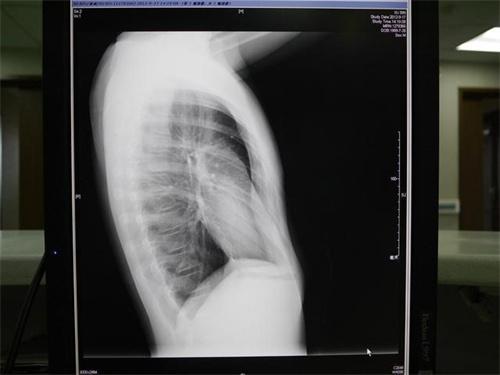

顧海濤教授仔細觀察后發現小安胸骨下段,以及肋骨都向內凹陷呈現漏斗這樣的形狀,這種情況是先天胸廓畸形也是常說的漏斗胸,胸骨下段會向內凹陷外觀形似漏斗。孩子比較小的時候,癥狀不明顯時,大多數家長都容易把漏斗胸當成孩子缺鈣耽誤了治療。

伴隨著孩子生長發育,胸廓凹陷的情況會進一步加重,有些家長很可能并沒有意識到問題所存在的嚴重性,認為僅僅是美觀上出現了問題,直到進入學齡期后都沒有積極就診治療,從而最終帶來較為嚴重的后果,一旦發現孩子胸廓形態有異常,要及時前往醫院就診,以免延誤了最佳治療的時間。